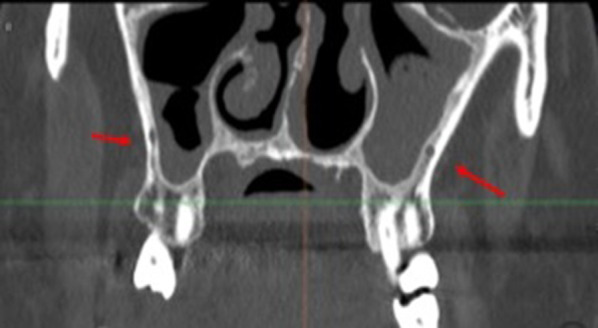

Fig. 1.

Anatomical structures evaluated: PSAA variations (A) 1–2–3; (B) MSS, (C) CS

Fig. 2.

Different variations of PSAA (I/Intrasinus; II/Intraosseous) seen in sagittal planes

Fig. 3.

CS branches course from the infraorbitary canal to the hard palate in the maxilla seen in different planes (axial, frontal, sagittal)